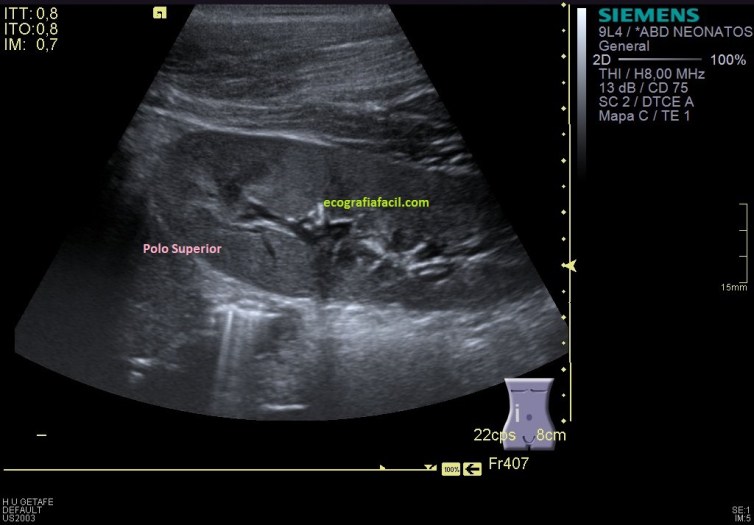

Es una imagen la 1 donde vemos un riñón derecho cuyo acceso es posterior, es decir, con la paciente en decúbito prono, usando una sonda lineal de alta frecuencia, con apertura de campo de visión (trapezoide), simulando una sonda cónvex, pero fíjate en la porción superior de la imagen como la sonda es lineal.

Para empezar el riñón está ligeramente más bajo de lo habitual, pero morfológicamente es precioso, se objetiva fenomenal, cortamos ambos polos, por el tamaño de casi 9 cms, nos habla de un paciente pediatricx, pero en torno a los 10 años. Sin son delgados, recomiendo siempre acceso posterior, paralumbar. Se observa la musculatura y el riñón, en este caso homogéneo y morfológicamente normal.

Como en la imagen 1 no he podido ver los polos, tengo que poder demostrarlos aunque tenga que estudiarlos de modo individual, polo superior en una,imagen 2 y polo inferior en otra, imagen 3.